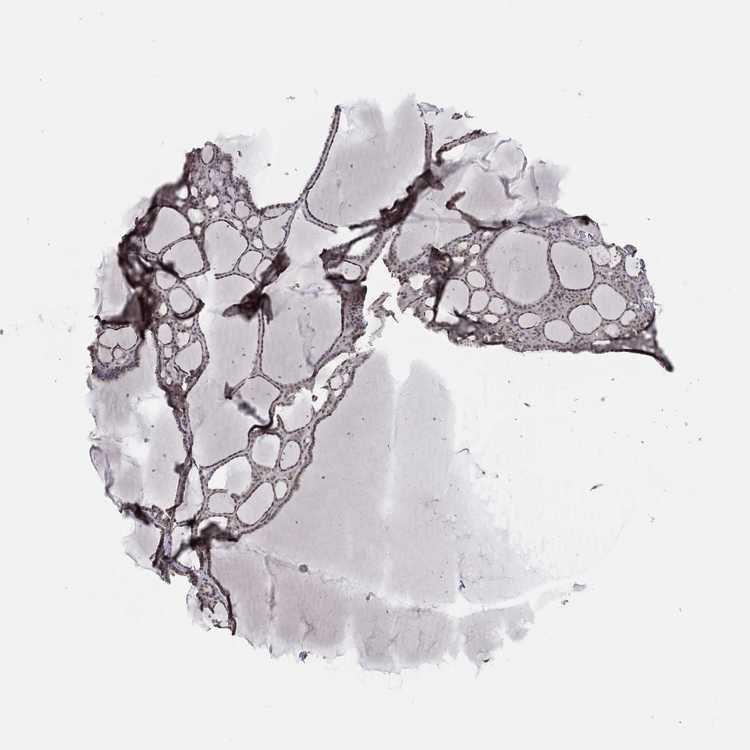

THYROID GLAND - Antibody stainingi

Antibody staining in the annotated cell types in the current human tissue is reported as not detected, low, medium, or high, based on conventional immunohistochemistry profiling in selected tissues. This score is based on the combination of the staining intensity and fraction of stained cells.

Each image is clickable and will lead to virtual microscopy that enables deeper exploration of all samples and also displays staining intensity scores, fraction scores and subcellular localization as well as patient and tissue information for each sample.

Antibody HPA028539Antibody HPA061094

Glandular cells MediumNot detected